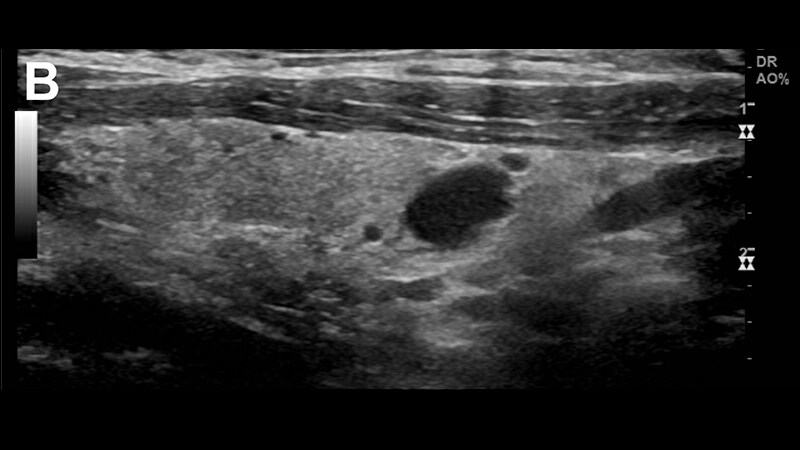

Thyroid Cancer